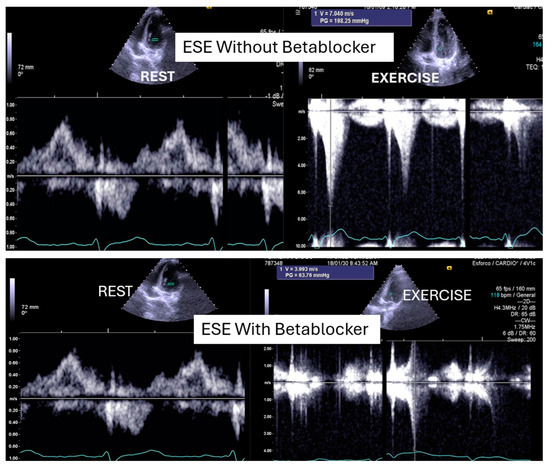

We read with interest the excellent review manuscript from Huang, S.-W. and Liu, Y.-K. [1], which describes that pediatric chest pain is a common chief complaint in the emergency department. Not surprisingly, children with chest pain are usually brought to the emergency department by their parents out of fear of heart disease. However, chest pain in the pediatric population is generally a benign disease. In this review, we have identified musculoskeletal pain as the most prevalent etiology of chest pain in the pediatric population, accounting for 38.7–86.3% of cases, followed by pulmonary (1.8–12.8%), gastrointestinal (0.3–9.3%), psychogenic (5.1–83.6%), and cardiac chest pain (0.3–8.0%). Various diagnostic procedures for cardiac chest pain are commonly used in the emergency department, including electrocardiogram (ECG), chest radiography, cardiac troponin examination, and echocardiography. However, these examinations demonstrate limited sensitivity in identifying cardiac etiologies, with sensitivities ranging from 0 to 17.8% for ECG and 11.0 to 17.2% for chest radiography. To avoid the overuse of these diagnostic tools, a well-designed standardized algorithm for pediatric chest pain could decrease unnecessary examination without missing severe diseases [2,3,4]. Our primary concern is that no attention has been given to exercise-induced intraventricular gradients, which are easily detectable using exercise stress echocardiography and have been associated with chest pain and other symptoms [5,6,7,8,9,10,11,12,13], including in children. We present the case of a 15-year-old boy, a rugby player, who experienced severe chest pain followed by syncope during a match. Upon evaluation at the emergency department, he showed a significant increase in troponin levels. Coronary angiography (Figure 1) and CT angiography (Figure 2) revealed normal results. However, an exercise stress echocardiogram identified a significant intraventricular gradient (Figure 3).

This was considered the most likely cause of the clinical event. This test was repeated under bisoprolol therapy. In our experience with 139 athletes [11], 58 (41%) were under 18 years old—46 of whom were evaluated for exercise-related symptoms—and 20 (34%) developed an intraventricular gradient during exercise. We strongly advocate for exercise stress echocardiography to be considered for children presenting with exercise-related symptoms in the emergency department at the appropriate time. According to our experience [8], approximately 40% of children with clear exercise-related symptoms, like angina, dizziness, syncope, ST alterations in ECG, or ST alterations in exercise stress ECG (Figure 4), develop mid-ventricular obstruction (MVO) (Figure 5), which appears to be a relatively high prevalence; we recognize this warrants further explanation regarding the mechanisms of development and relationship to chest pain.

In our experience and in the literature [5,6,7,8,9,10,11,12,13,14,15,16], chest pain (exercise angina) has been related to an anatomically small LV chamber, small LVOT, and to an increased relative wall thickness. Additionally, a certain level of hypohydration—characterized by a reduction in left ventricular volumes and commonly linked to intense exercise—may be a potential contributing factor to MVO.As most of the children were referred by other centers, these children were not systematically followed up longitudinally. However, it is our knowledge that four have participated in the genetic study for myocardiopathy and one developed HCM [10]. The increase in intraventricular pressure causing perturbation in subendocardial perfusion is the potential mechanism for ischemia, chest pain, and ST alterations [15,16]. Furthermore, using beta-blockers in children without structural cardiac abnormalities remains a controversial approach. The use of beta-blockers [17,18] is recommended and suitable for pediatric arrhythmias, hypertension, heart failure, hypertrophic cardiomyopathy, migraine prophylaxis, hyperthyroidism, and infantile hemangiomas. Beta-adrenergic receptor antagonists, commonly known as beta-blockers, are divided into three generations based on their receptor selectivity. First-generation beta-blockers (e.g., propranolol) are non-selective and block both β1 and β2 receptors. Second-generation beta-blockers (e.g., metoprolol) are relatively selective for the β1 receptor, while third-generation beta blockers (e.g., carvedilol) block β1, β2, and α1 receptors. Beta-blockers are frequently used to treat adult cardiac conditions, such as hypertension, atrial arrhythmias, and chronic heart failure. Similarly, they are considered a first-line treatment for many pediatric tachyarrhythmias, both in non-operative and peri-operative settings [19]. However, despite their widespread use in children, there is a significant lack of pediatric-specific data to determine precise dosing and personalized treatment. As a result, most pediatric treatment decisions are based on data extrapolated from adult studies. The most commonly prescribed oral beta-blockers for children include atenolol, carvedilol, metoprolol, propranolol, and bisoprolol [19]. The use of beta-blockers is recommended for adult patients with exercise-induced IVPG, whether or not they have hypertrophic cardiomyopathy [20,21,22,23,24]. Based on both our findings and the existing literature, we suggest that children would also benefit from the same treatment (Figure 3).

Figure 3. An intraventricular-induced gradient in one child with chest pain followed by syncope during a rugby match. In the upper image, there is a huge intraventricular gradient and in the lower image, there is a small intraventricular gradient under treatment with bisoprolol.